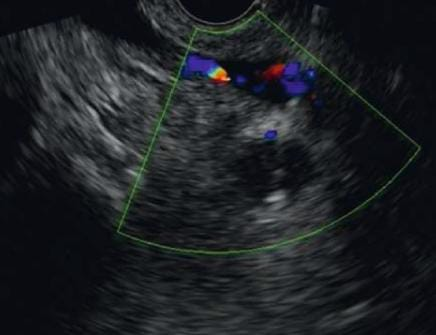

A TVNA é uma técnica de punção por agulha fina em que a agulha atravessa um vaso sanguíneo interposto (como a aorta, artéria pulmonar ou veia cava) para alcançar uma lesão torácica ou abdominal.

- Guia: ecoendoscopia em tempo real com doppler

- Estudo cuidadoso com doppler